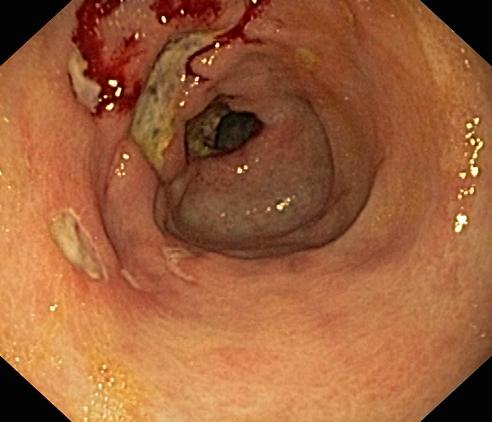

Wrzód trawienny